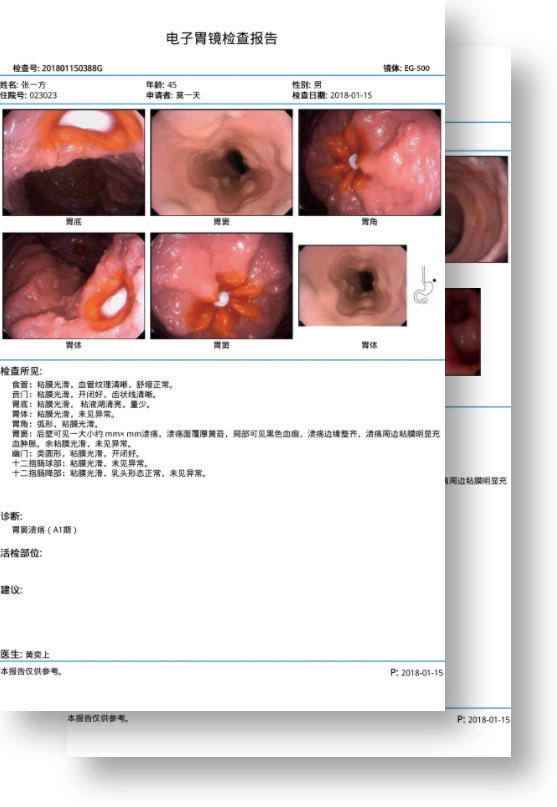

百万级像素高清传感器,1080P全高清视频信号输出,图像清晰。

能够凸显黏膜浅层和中层血管轮廓,适用于中、远景观察下的病灶识别和早癌筛查。

能够凸显黏膜浅层血管轮廓和黏膜表面微结构,适用于中、近景观察下的早癌精确诊断。

弯曲角度大,方便观察食管下段贲门、胃底部等难以观察到的部位,减少盲区。